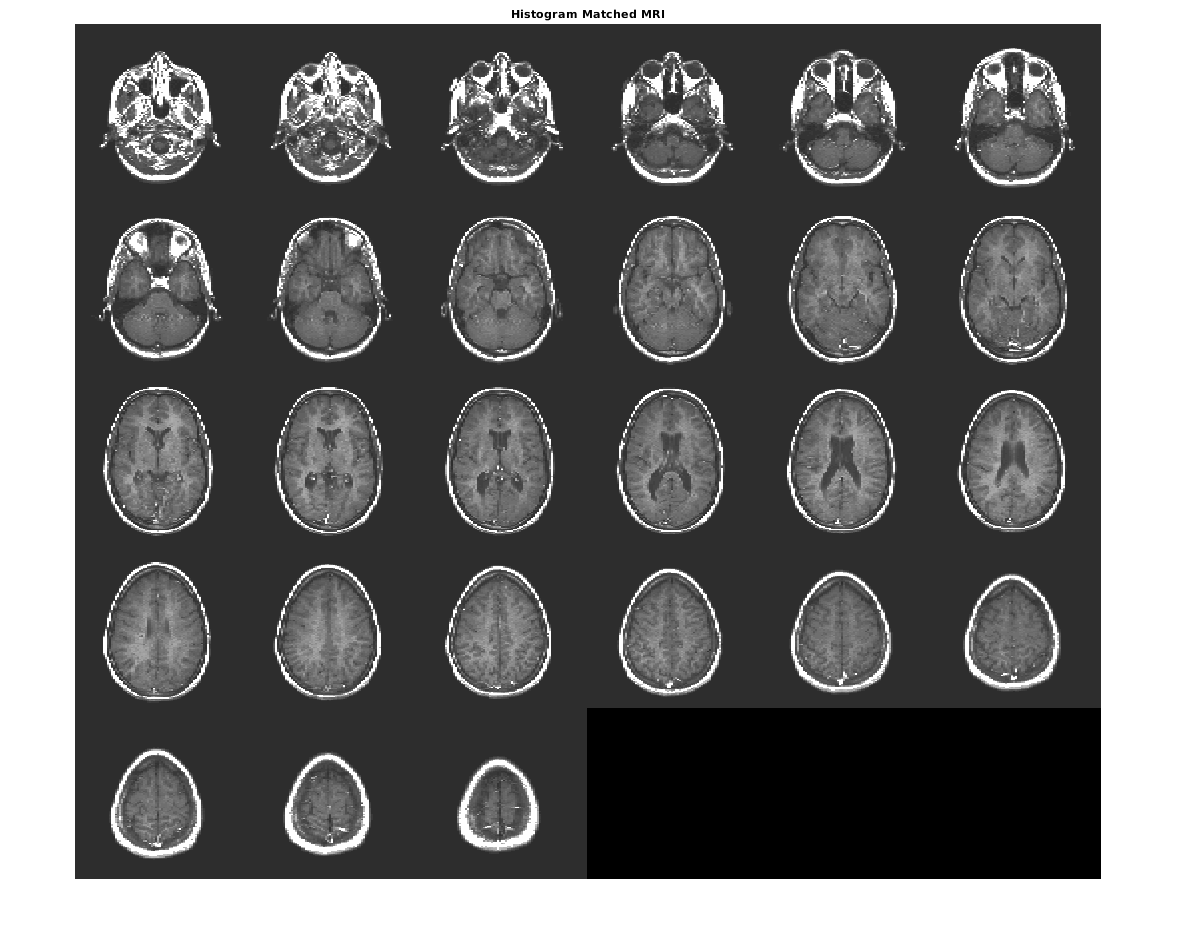

Совпадайте с гистограммой D к гистограмме полноразмерного ref.

Dmatched = imhistmatchn(D,ref);

Отобразите вывод. Заметьте, что уровни яркости выхода более тесно совпадают со ссылочным изображением, чем оригинальное изображение.

figure

montage(Dmatched,'DisplayRange',[])

title('Histogram Matched MRI')

Figure contains an axes object. The axes object with title Histogram Matched MRI contains an object of type image.